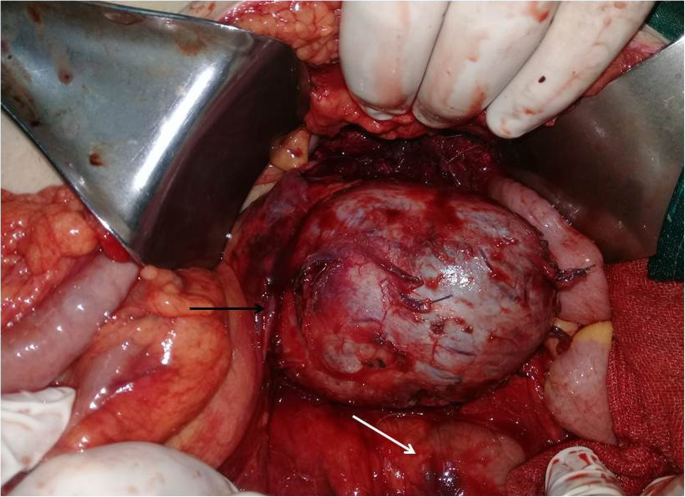

Preoperative assessment revealed controlled vital signs. During the induction of general anaesthesia and intubation, all vital signs remained normal. When midline incision was preformed, BP and pulse started shooting up (220\130–250\145) mmHg and (120–135) bpm respectively. To control hypertension, deepening the anaesthesia was performed by administration of sedative and analgesic drugs, in addition to vasodilator drugs. The decision was taken to perform minimal manipulation mass excision. At first, the mass appeared to be retroperitoneal adherent to the 4th segment of the duodenum and Treitz ligament with hypervascularized surface and strict adherence posteriorly (Fig. 4). The mass showed neovascularisation from the duodeno-jejunal junction with dense adhesion with the 4th segment of the duodenum without invasion (Fig. 5). Thereafter, the mass was found to be located paravertebral between the aorta and the left kidney and separated from the left kidney and the left adrenal gland. During careful dissection of the mass posteriorly of the aorta and the fatty tissue of the left kidney (Fig. 6), BP and pulse were around (180\110–240\135) mmHg and (130–145) bpm respectively. When the mass main draining vein was ligated, BP dropped dramatically to (50\30) mmHg, so high amounts of crystalloid and vasoconstrictive agents were applied. Due to the mass invasion, an injury of the left renal vein occurred and repair of the vein was carried out. 2000 ml of blood lost and six blood units were transfused. The patient was observed in intensive care unit for 24 h and her vital signs stayed stable. Postoperative course was uneventful. The patient was discharged home on postoperative day six. The histopathology study raised a suspicion of paraganglioma (Figs 7, 8). The immunohistochemical staining studies were positive for neuroendocrine markers chromogranin, synaptophysin, NSE and CD56 (Figs. 9, 10). S100 marker and CK were negative (Fig. 11) and Ki67 marker showed low mitotic index (Fig. 12). Lastly, the diagnosis of paraganglioma was confirmed. All medications were stopped. After 3 months, her follow up was normal. Written informed consent was obtained from the patient.